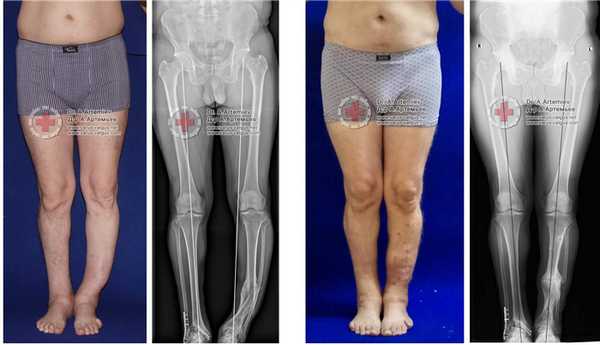

Достаточно грубая варусная деформация у девушки 25 лет исправленная при помощи метода Илизарова. У аппаратной методики есть важное преимущество, она позволяет производить коррекцию в любых плоскостях, одновременное увеличение длины, и одновременно проводить вмешательство на обеих нижних конечностях. Аппарат Илизарова можно спрятать под свободными брюками, и ходить без трости или костылей. Подобная операция не только является профилактикой развития в последующем гонартроза с поражением внутренних отделов коленных суставов, но так же значительно влияет на эстетику нижних конечностей, что крайне важно, когда мы говорим о девушках.

Ещё один клинический пример, одновременного исправления угловой, ротационной деформации и укорочения левой голени. Травма за 5 лет до операции в результате падения с 5 этажа, левая голень срослась с грубой варусной деформацией, удлинением и внутренней ротацией, правая нога укоротилась за счёт явлений посттравматического артроза голеностопного сустава. В итоге ноги получились вот такими. Обращало на себя внимание, что деформированная левая голень длиннее правой. При выпрямлении эта разница стала бы еще более заметной. В итоге решили укоротить левую голень и выпрямить её. Резецировали около 5 см берцовых костей и срастили их в прямом положении. Устранили варус и внутреннюю ротацию.